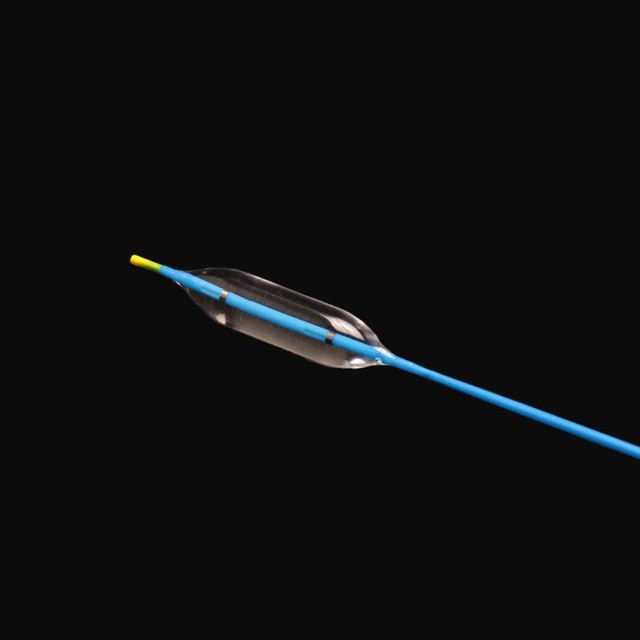

● Elastic yakapfava tip dhizaini, iyo inogona kupinda mukati medu pachinzvimbo chakanangana nechinzvimbo chisina kukuvara {}

● Kugadzira kurongeka kwehubhu kunoita kuti zvive zvatakapfidza uye nezvakanaka zvakanaka, zvinokatyamadza kupokana nekukasira uye kupfuudza nyore nyore .

● Iyo adigaque mamaki pamigumo miviri yeballoon inogona kupa chaiyo chinzvimbo pasi pe x-ray .

● Pre-input 0 . 035 "kutungamira waya neye nyoro nyoro uye mucherechedzo, iri nyore kufungidzira urefu hwemukati wemukati waya.